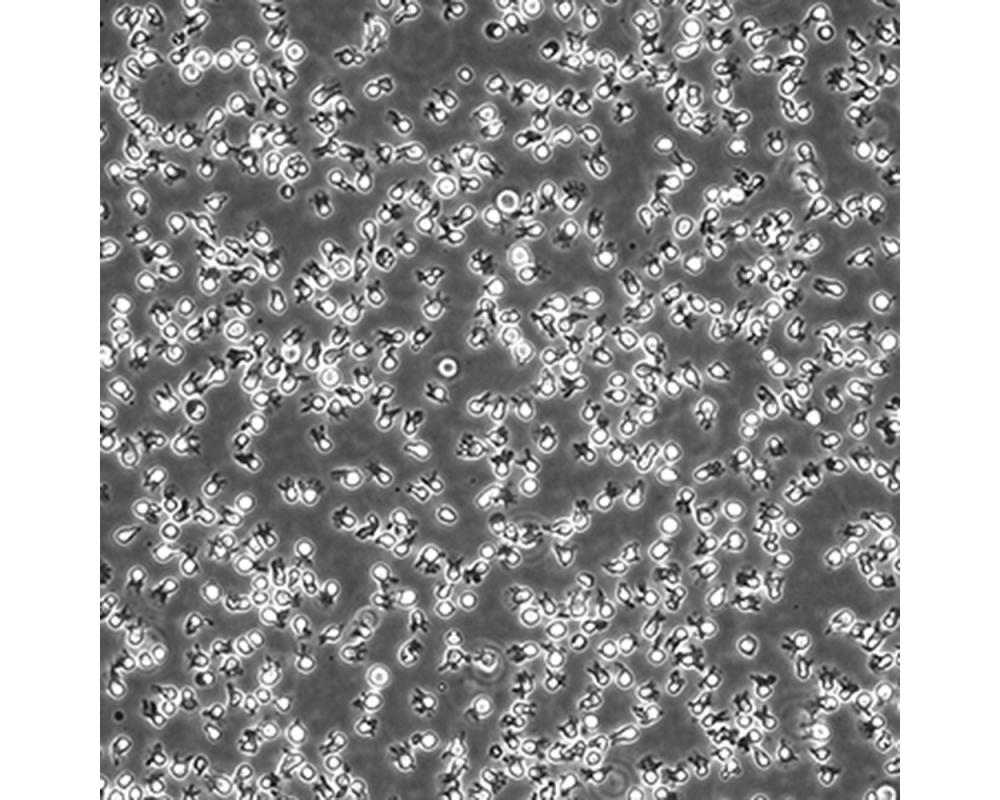

中文名稱 人彌漫大B細胞淋巴瘤細胞

組織來源 彌漫大B細胞淋巴瘤;男性

生長特性 懸浮

培養基 IMDM,90%;FBS,10%;雙抗。

培養條件 Atmosphere: Air, 95%; CO2, 5%。Temperature: 37℃